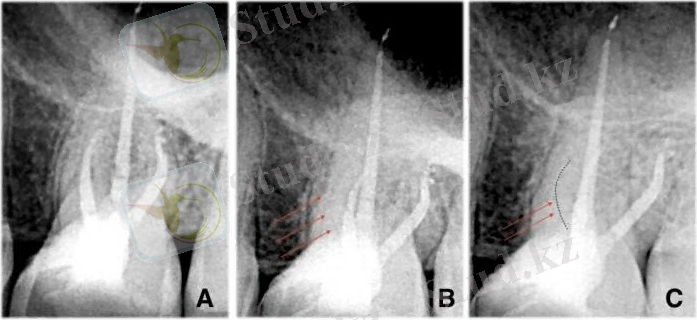

Рентгенография MB2 іздеуде өте маңызды.

Көптеген стоматологтар бір рентген суретпен ғана жұмыс істей береді. Бұл жеткіліксіз. Үш түрлі бұрыштан рентгенография жасаған кезде (SLOB техникасы) біз тістің құрылымын жақсы көре аламыз. Қателіктер болмас үшін файлдарды қолдану тізбегін жоспарлау маңызды. Fanta Af F1 файлдары гибридті термиялық өңдеудің және тегіс беттің арқасында өте тар каналдарды қалыптастырудың қауіпсіз құралы болып саналады. Тіс қуысына еркін кіру алаңы барлық эндодонтиялық манипуляциялардың алғашқы қадамы екені белгілі және ол әрқашан маңызды. Жақсы жұмыс істеу үшін тегістелген және тазартылған осьтік қабырғаларға толық кіру алаңы қажет. Кіру алаңы үлкен болуы керек деп айтпаймын, сау тіс құрылымын бұзбай жеткілікті қол жеткізуге болады. Кейде жақсы қол жеткізу үшін барлық кіру алаңын қалпына келтірулерді, соның ішінде тәждерді алып тастау қажет.